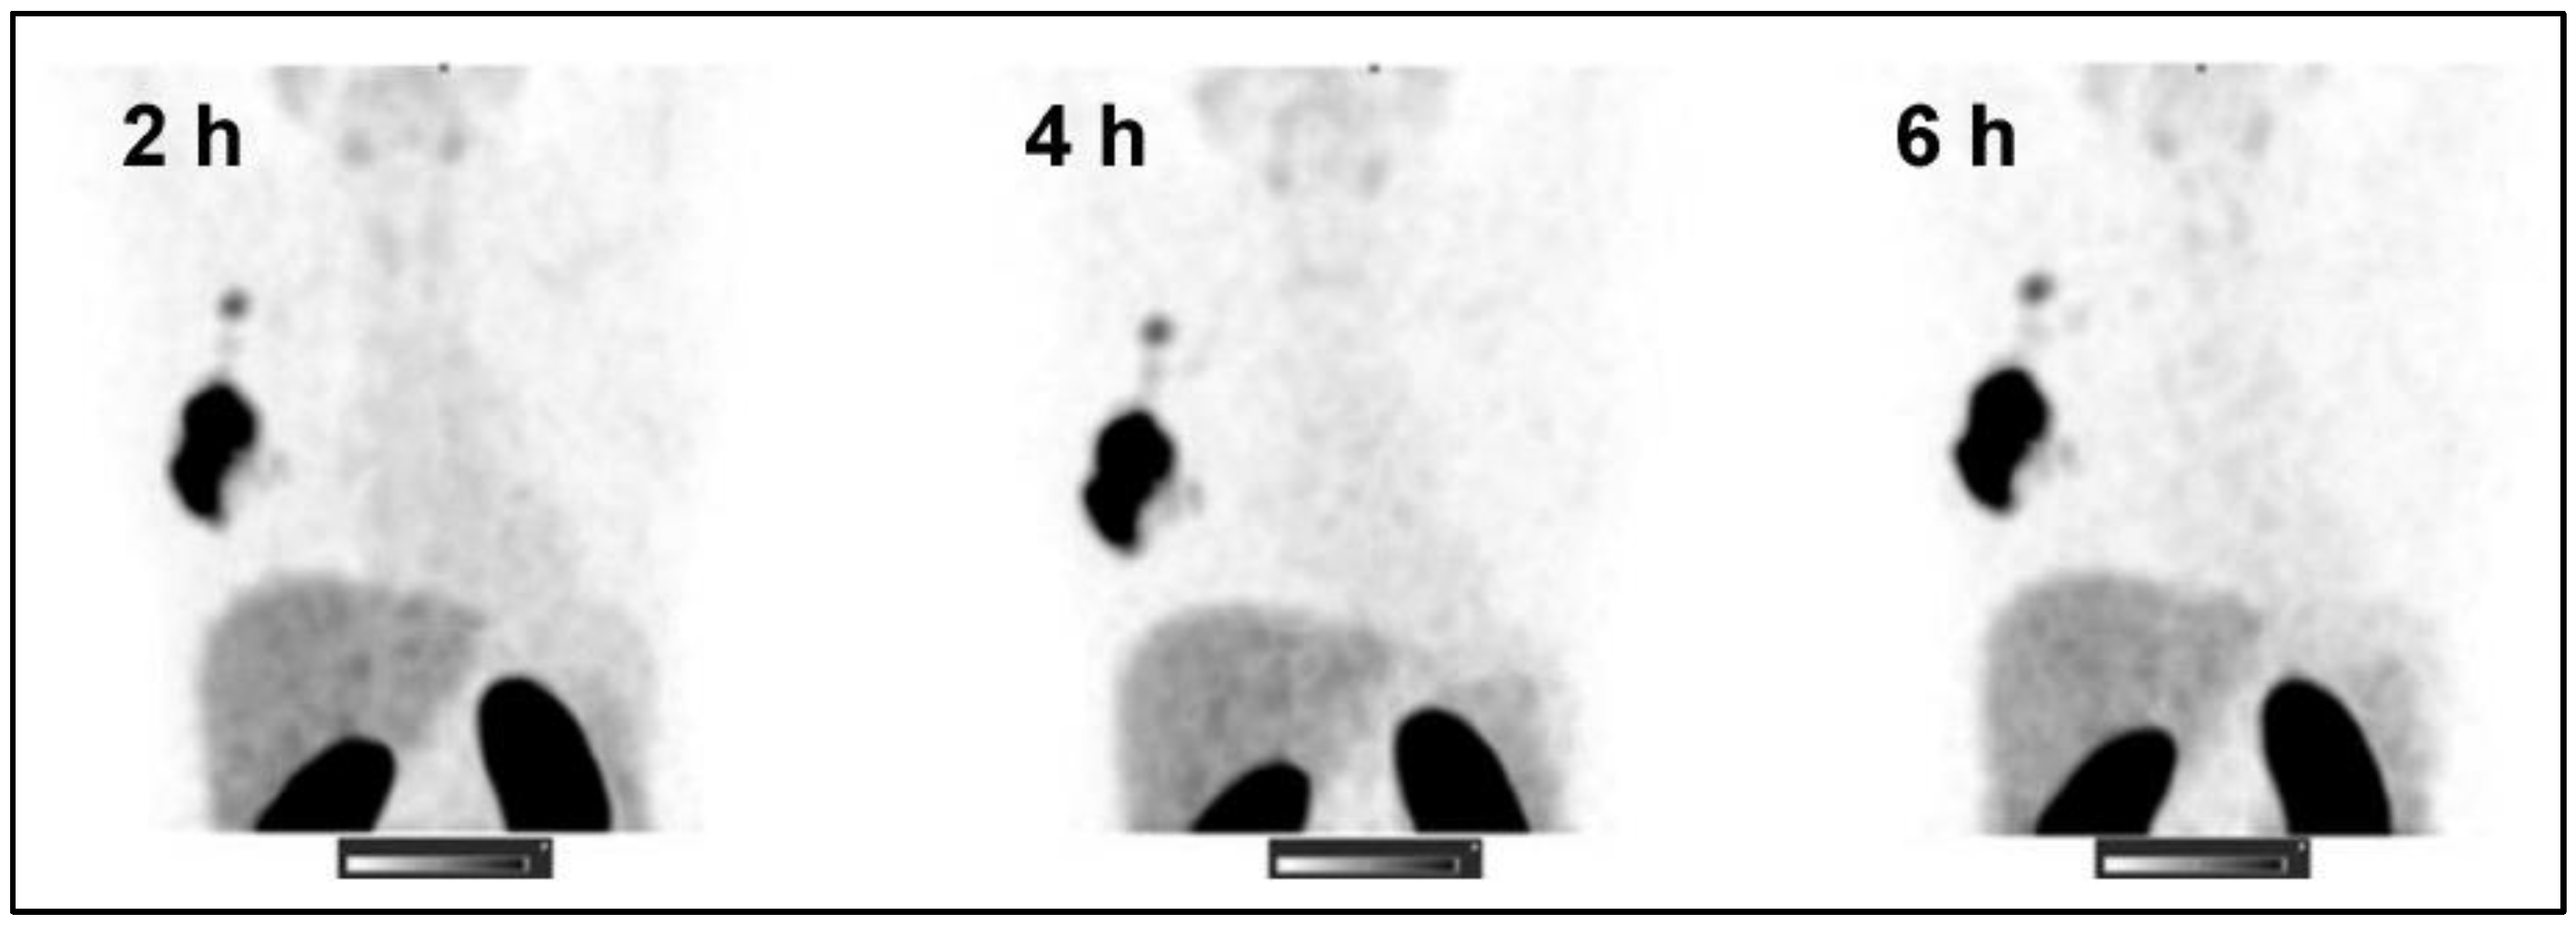

- Bragina, O.; Chernov, V.; Larkina, M.; Rybina, A.; Zelchan, R.; Garbukov, E.; Oroujeni, M.; Loftenius, A.; Orlova, A.; Sorensen, J.; et al. Phase I clinical evaluation of (99m)Tc-labeled Affibody molecule for imaging HER2 expression in breast cancer. Theranostics 2023, 13, 4858–4871. [Google Scholar] [CrossRef] [PubMed]